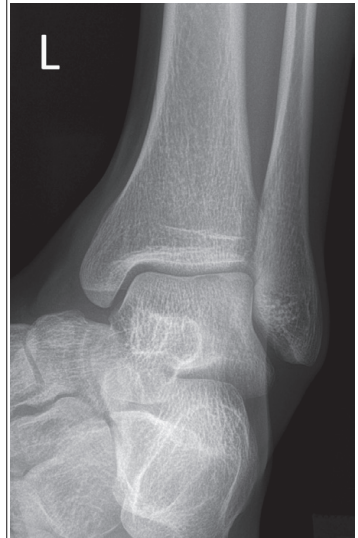

tibia superimposes more than ½ of the fibular, medial mortise is closed

Anterior tibial margin is lateral to posterior margin

External rotation

tibia superimposes less than ½ of fibula, medial mortise is closed

Posterior tibial margin is lateral to anterior and is superimposed by talus

Internal rotation

What are issues with this mortise ankle?

Insufficient obliquity/ under-rotated

the tibia superimposes more than 1/4 of the fibula, and the lateral and medial mortises are closed

What are the issues with this mortise ankle?

the tibia superimposes less than 1/4 of the fibula, and the lateral and medial mortises are closed

Excessive obliquity/ over-rotated